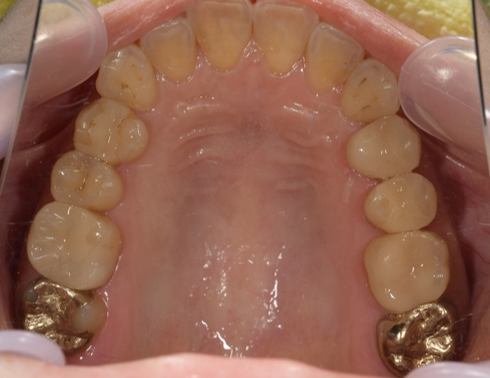

治療前-治療後